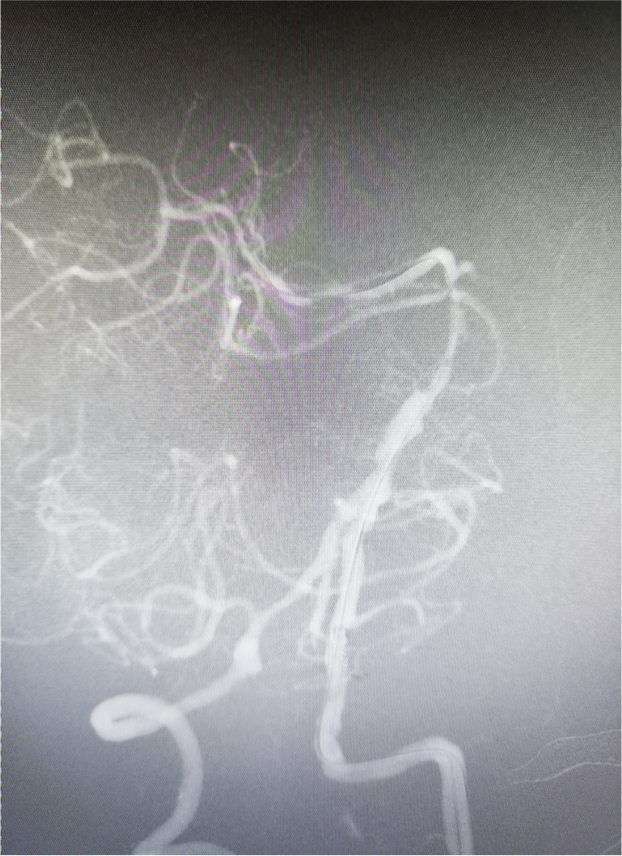

造影显示基底动脉远端闭塞,建立血管内治疗通路:Locaste长鞘同轴带领Skathi远端通路导管到位。

微导丝超选至右侧大脑后动脉,微导管通过狭窄段困难。考虑原位狭窄,行球囊扩张。